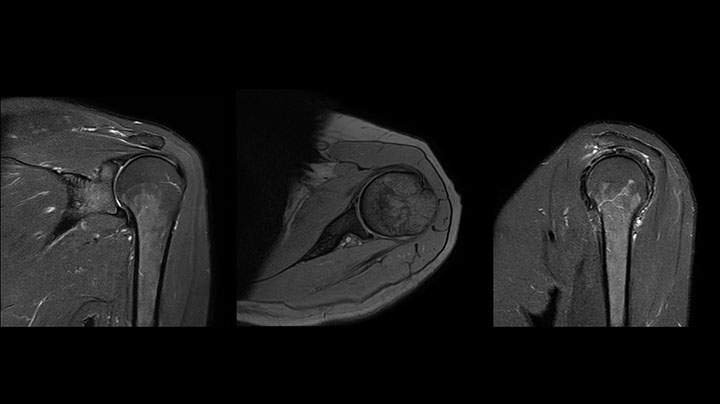

Shoulder MRI with high quality, large coverage

The Prodiva shoulder coil is very flexible and has large coverage, which makes good positioning easier, and that contributes to the superb image quality and high SNR that we get in our shoulder exams.

Scan time 2:55 min, FOV 160 mm,

acq voxels 0.55 x 0.83 x 3.0 mm.

Scan time 4:19 min, FOV 160 mm,

acq voxels 0.55 x 0.80 x 3.0 mm.

Scan time 2:50 min, FOV 160 mm,

acq voxels 0.70 x 0.99 x 3.0 mm.

Shoulder MRI with high quality, T2 SPIR

Shoulder MRI with high quality, STIR TSE